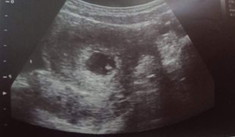

ตั้งครรภ์ได้ 9 อาทิตย์ หมอซาวด์ดูลูก ไม่มีการเจริญเติบโต มีโอกาสไข่ฝ่อ 60% ควรทำอย่างไรดี